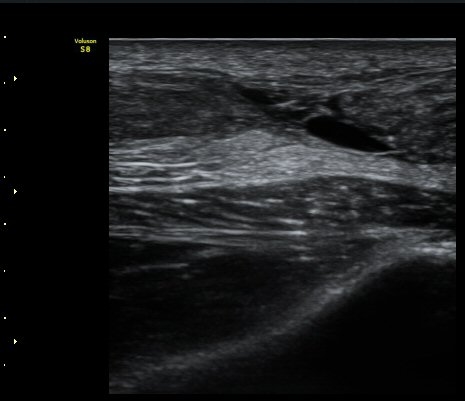

[¹ß¸ñ] ¾ÆÅ³·¹½º ÈûÁÙ ÆÄ¿­ÀÇ ÃÊÀ½ÆÄ Áø´Ü

ÁÂÃø ¹ß¸ñÀÇ ÅëÁõ(2ÁÖ)

2ÁÖ Àü ¹èµå¹ÎÅÏÇÏ´Ù°¡ ¹ß¸ñÀÇ ÅëÁõÀÌ ¹ß»ýÇÏ¿© Ÿº´¿ø¿¡¼­ ÃÊÀ½ÆÄ°Ë»ç µî ½ÃÇàÇÏ°í ºÎ¸ñ°íÁ¤ ÈÄ ¹°¸®Ä¡·á À§ÇØ ³»¿ø

¾ÆÅ³·¹½º°Ç ºÎÁ¾ ¹× ¾ÐÅë, ´Éµ¿Àû ¹ß¸ñ ¹ß¹Ù´ÚÃø ±¼°ñ G 1, thomson test(+).

ÃÊÀ½ÆÄ °Ë»ç